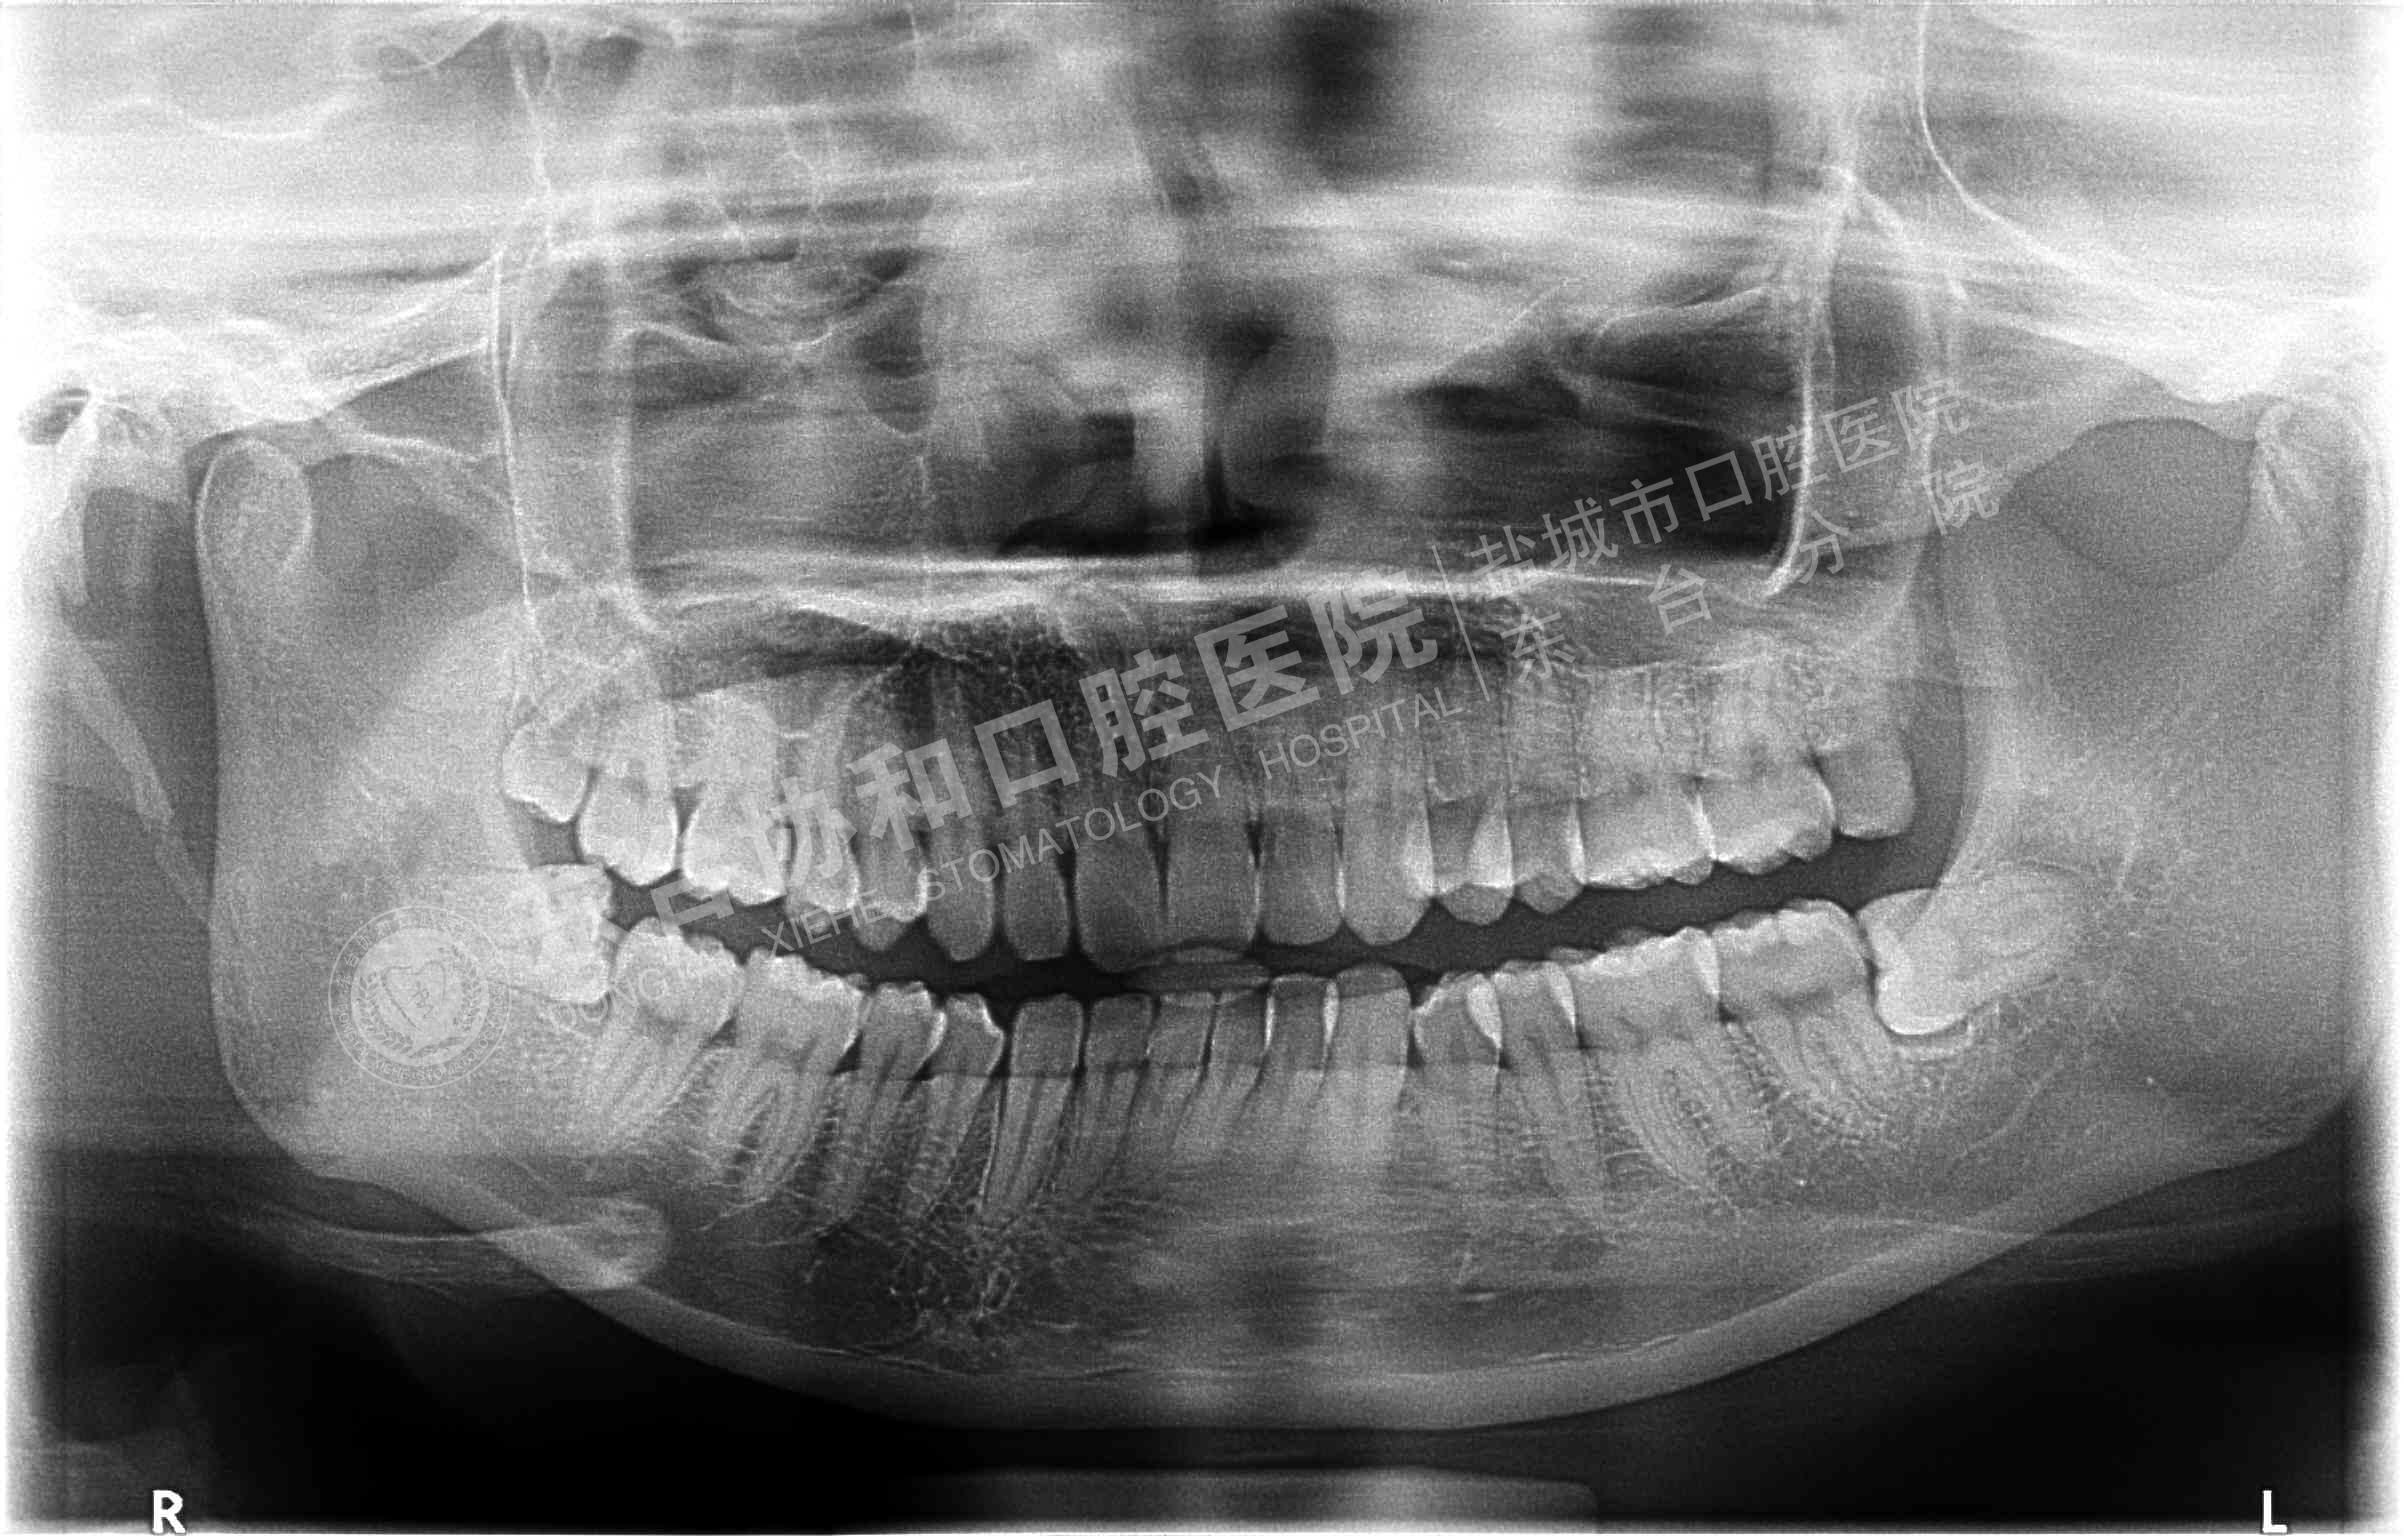

很多患者都很排斥拍牙片,認(rèn)為醫(yī)院是為了多收錢才讓他們拍的,其實(shí)這是一個(gè)錯(cuò)誤的想法,拍牙片是口腔科常用重要的檢查手段,臨床檢查只能直觀判斷牙冠和牙齦部分的情況,而對(duì)于牙根,牙槽骨、牙周膜等情況則必須通過牙片檢查。牙齒在牙片上顯示出白色阻射影像,其中牙釉質(zhì)阻射強(qiáng),牙本質(zhì)和牙骨質(zhì)阻射低于牙釉質(zhì),牙髓腔呈灰黑色影像,根管口至根尖孔呈逐漸變細(xì)的影像。

不同病種拍牙片的意義1、頜面部外傷:了解牙齒是否折裂、牙槽骨骨折程度和范圍。

2、牙齒硬組織病變:牙頸部牙根部齲齒、鄰面齲、確定齲壞的程度和齲壞的范圍;齲壞深度與牙髓腔的關(guān)系;了解齲壞與牙髓腔的距離;了解髓腔的變化情況和根尖周情況。

4、根尖周炎癥:了解病牙根管情況:如根管數(shù)目、粗細(xì)、彎曲度以及有無鈣化、有無內(nèi)吸收等情況;根管調(diào)節(jié)后的充填情況。如果牙齒需要做根管調(diào)節(jié),則牙片需要拍三張以上。調(diào)節(jié)前拍片是用來判斷是否根尖炎或者是囊腫的大小、范圍等,判斷是否需要根管調(diào)節(jié);根管預(yù)備術(shù)中片,檢查根管調(diào)節(jié)的長(zhǎng)度,調(diào)節(jié)后評(píng)價(jià)根管調(diào)節(jié)成功與否。

5、牙周炎癥:顯示牙槽骨吸收范圍和破壞程度。

9、拔牙檢查牙根情況以及牙槽骨破壞程度,牙齒是否拔除干凈以及牙槽窩形態(tài)是否完好。